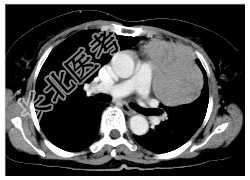

- [材料题] 病历摘要:女,56岁。因胸部不适,2月来诊,无发热,无咯血。起病以来体重明显减轻。查体:左胸呼吸音减弱,左上胸扣诊浊音。胸部X线片示“左上肺占位病变”。做胸部CT线检查。

- 简答题1、诊断及依据是什么?

- 简答题2、鉴别诊断有哪些?